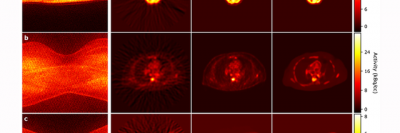

Our researchers have pioneered the use of imaging methods such as PET/CT, MRI, and live microscopy to observe and measure biological processes over time. By highlighting living cells or tissues with specific agents, we use these technologies to aid laboratory investigations into the root causes of cancer and to develop innovative approaches to improve diagnosis and treatment.